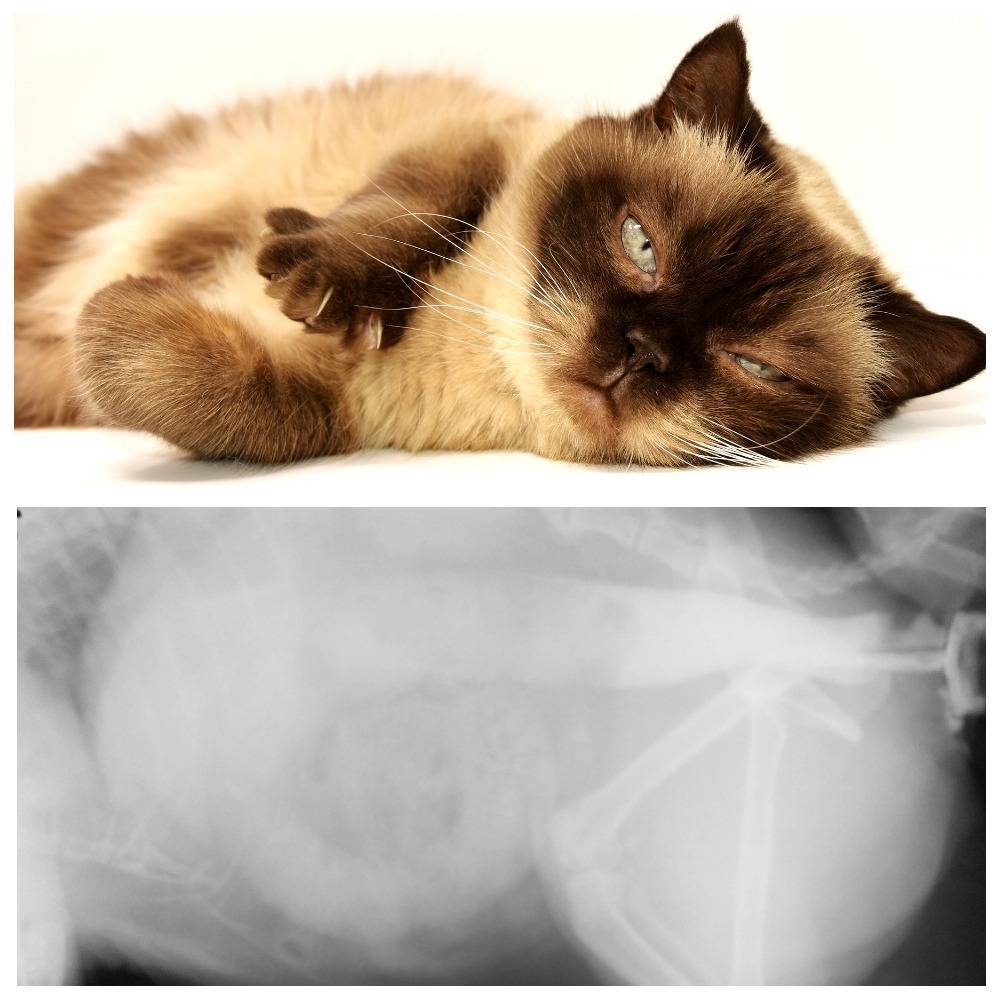

Чтобы быть уверенным в своем диагнозе, доктор назначает животному ренгтен.

Определить непроходимость кишечника у кота на первых порах самостоятельно достаточно затруднительно, из-за чего проблема усугубляется и может потребоваться проведение операции. При подозрительных симптомах обращаются к ветеринару, который визуально осмотрит кота и соберет детальный анамнез. Для подтверждения/опровержения диагноза потребуются следующие диагностические манипуляции:

- лабораторное исследование урины и крови;

- УЗИ органов пищеварительного тракта;

- рентген брюшной полости;

- анализ каловых масс.